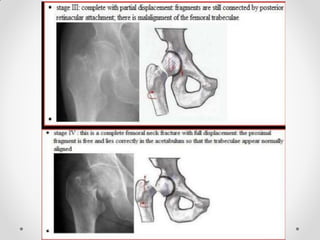

Plain radiograph

• Shenton’s line disruption (continuous line from medial edge of

femoral neck and inferior edge of the superior pubic ramus)

• lesser trochanter is more prominent due to external rotation

of femur

• femur often positioned in flexion and external rotation (due to

unopposed iliopsoas)

• asymmetry of lateral femoral neck/head

• sclerosis in fracture plane

• smudgy sclerosis from impaction

• bone trabeculae angulated

• nondisplaced fractures may be subtle on x-ray

Shenton’s line